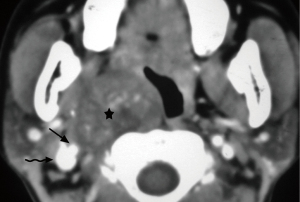

Lymphadenopathy is the most common pathology of the carotid space. A variety of primary diseases such as lymphoma, inflammation, and secondary diseases such as metastatic lymphadenopathy may involve lymph nodes, manifesting as masses of the carotid space. Enlarged lymph nodes, especially a solitary node, may mimic a primary tumor on CT and MRI. So, although the majority of lymphadenopathy is caused by metastatic tumors, we still describe them as “primary masses”. The imaging findings of diseased lymph nodes vary with different pathologies. Lymphoma may occur at any age with no gender difference, typically manifesting as painless or growing lymphadenopathy, and may have varying enhancement on CT/MRI imaging with extensive involvement and important neck structures encased yet without narrowing of arterial lumen (28-30). Metastatic lymphadenopathy is more frequently seen in middle-aged and elderly males and usually caused by head/neck squamous cell carcinoma, thyroid cancer, and so on. On CT/MRI imaging, it usually manifests as circular enhancement with central necrosis (squamous cell carcinoma), or obvious enhancement with cystic changes or calcification (thyroid cancer) (31-33). Lymph nodes in the carotid space lie anterior, lateral, and posterior to the jugular vein throughout its course in the neck (34). Therefore, enlarged lymph nodes in the carotid space will not be medial to any vessel in the carotid space (Figure 13), which is different from neurogenic tumors.